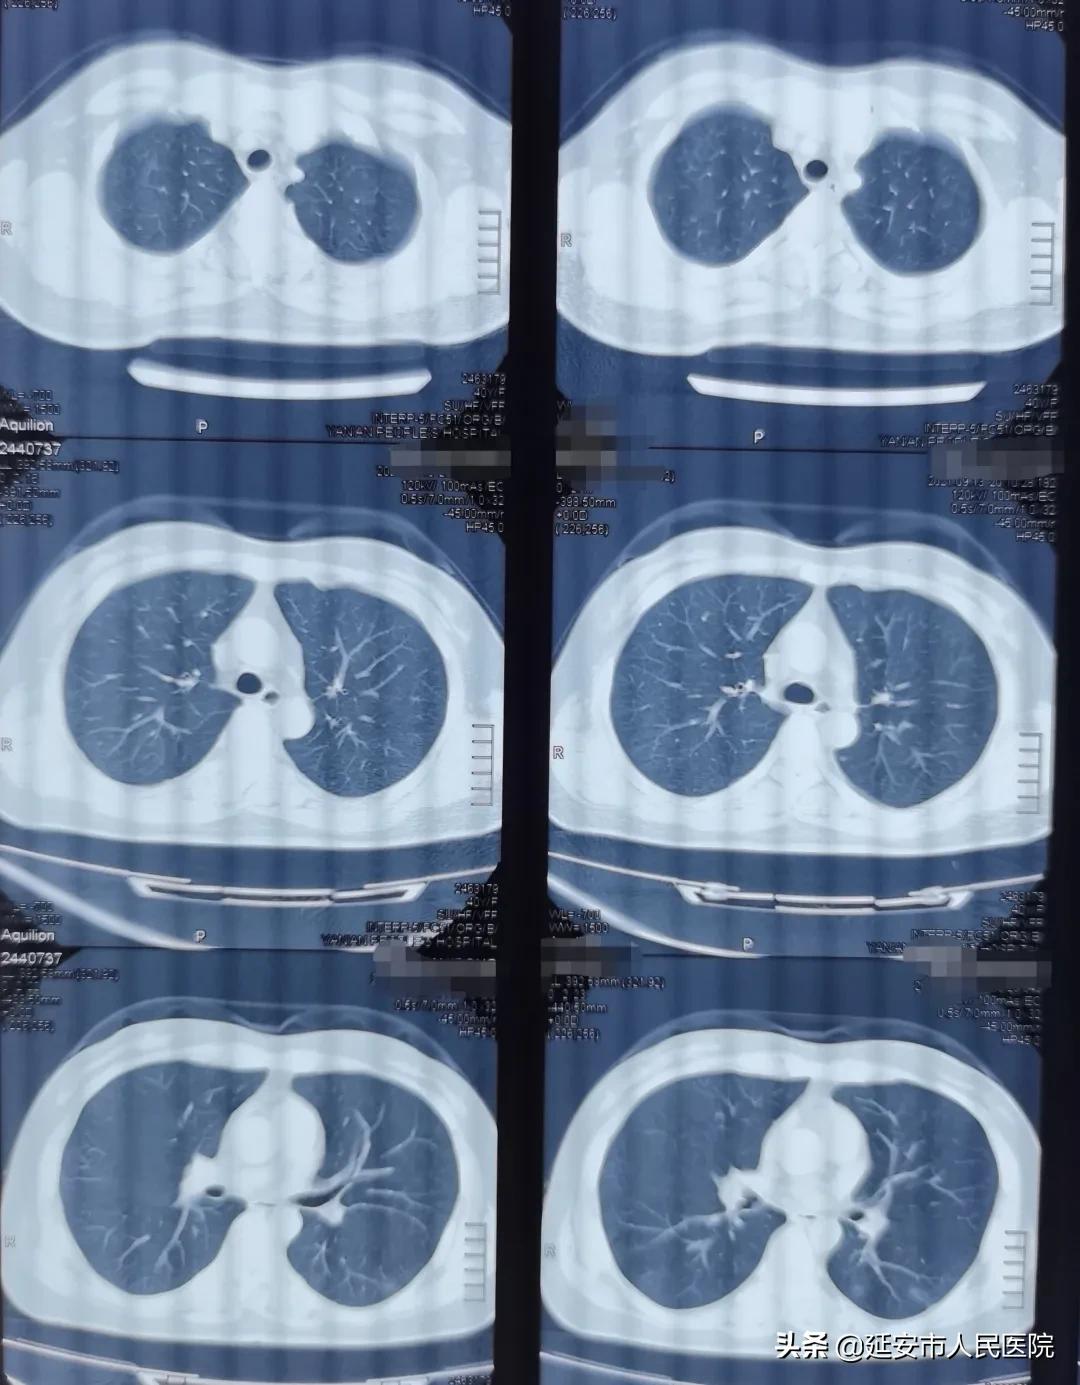

患者孙女士,今年40岁,确诊恶性淋巴瘤3月,第四疗程化疗结束,主因“发热3天,咳嗽、气短1天”入院,患者自诉3天前受凉后出现发热,最高体温40℃,无规律性,自行口服药物治疗无效,近1天出现咳嗽、气短,活动耐力明显下降,立即于延安市某医院查胸部CT示双肺以肺门为中心弥漫性的磨玻璃样改变,未行特殊处理,慕名找到中国医科大学延安医院副院长、医学博士、呼吸与危重症医学科学科带头人郑锐教授就诊。

郑锐教授仔细追问病史,认真阅片后,以“重症肺炎”收患者入院。郑锐教授分析:患者中年女性,有基础疾病淋巴瘤,曾行全身化疗,属于免疫受损宿主,起病急,症状重,肺部无阳性体征,结合患者胸部CT“弓月征”表现,诊断考虑肺孢子菌肺炎,但患者病情危重,免疫受损宿主还要注意混合感染可能,不能完全排除巨细胞病毒等感染;建议尽快完善动脉血气分析、外周血CD4+ T细胞、巨细胞病毒DNA、以及支气管镜肺泡灌洗NGS等检查,尽快寻求病原学确诊依据。

患者入院后立即完善血常规、常规C反应蛋白、降钙素原、免疫球蛋白、外周血CD4+ T细胞、巨细胞病毒DNA、呼吸道九项以及支气管镜肺泡灌洗NGS等相关检查,同时立即给予大剂量复方磺胺甲恶唑口服治疗。结果回报示:动脉血气分析示I型呼吸衰竭,巨细胞病毒DNA及呼吸道九项阴性,外周血CD4+ T细胞绝对计数小于200/ul,BALF NGS提示耶氏肺孢子菌,患者在最短时间被确诊,复方磺胺甲恶唑治疗1周后患者体温恢复正常,咳嗽、气短症状缓解,2周后复查胸部CT双肺弥漫性磨玻璃性病变基本完全吸收。